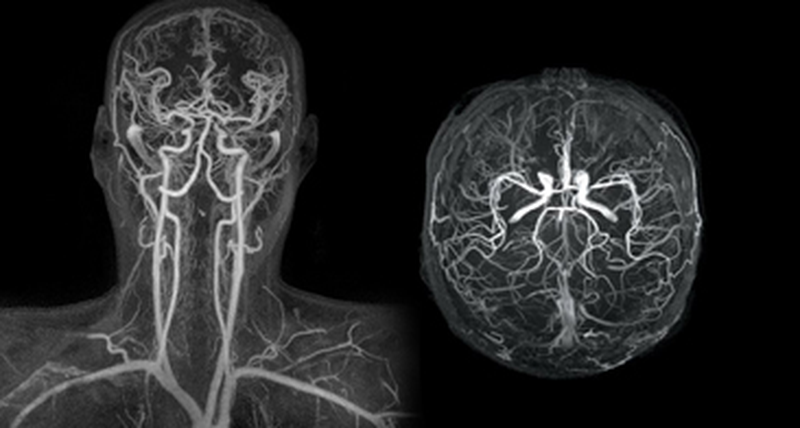

Η Μαγνητική Αγγειογραφία (MRA) είναι μια μη επεμβατική εξέταση που χρησιμοποιεί τη μαγνητική τεχνολογία και τους υπολογιστές για να δημιουργήσει λεπτομερείς εικόνες των αγγείων στο εσωτερικό του σώματος, συμπεριλαμβανομένων των αρτηριών και των φλεβών.